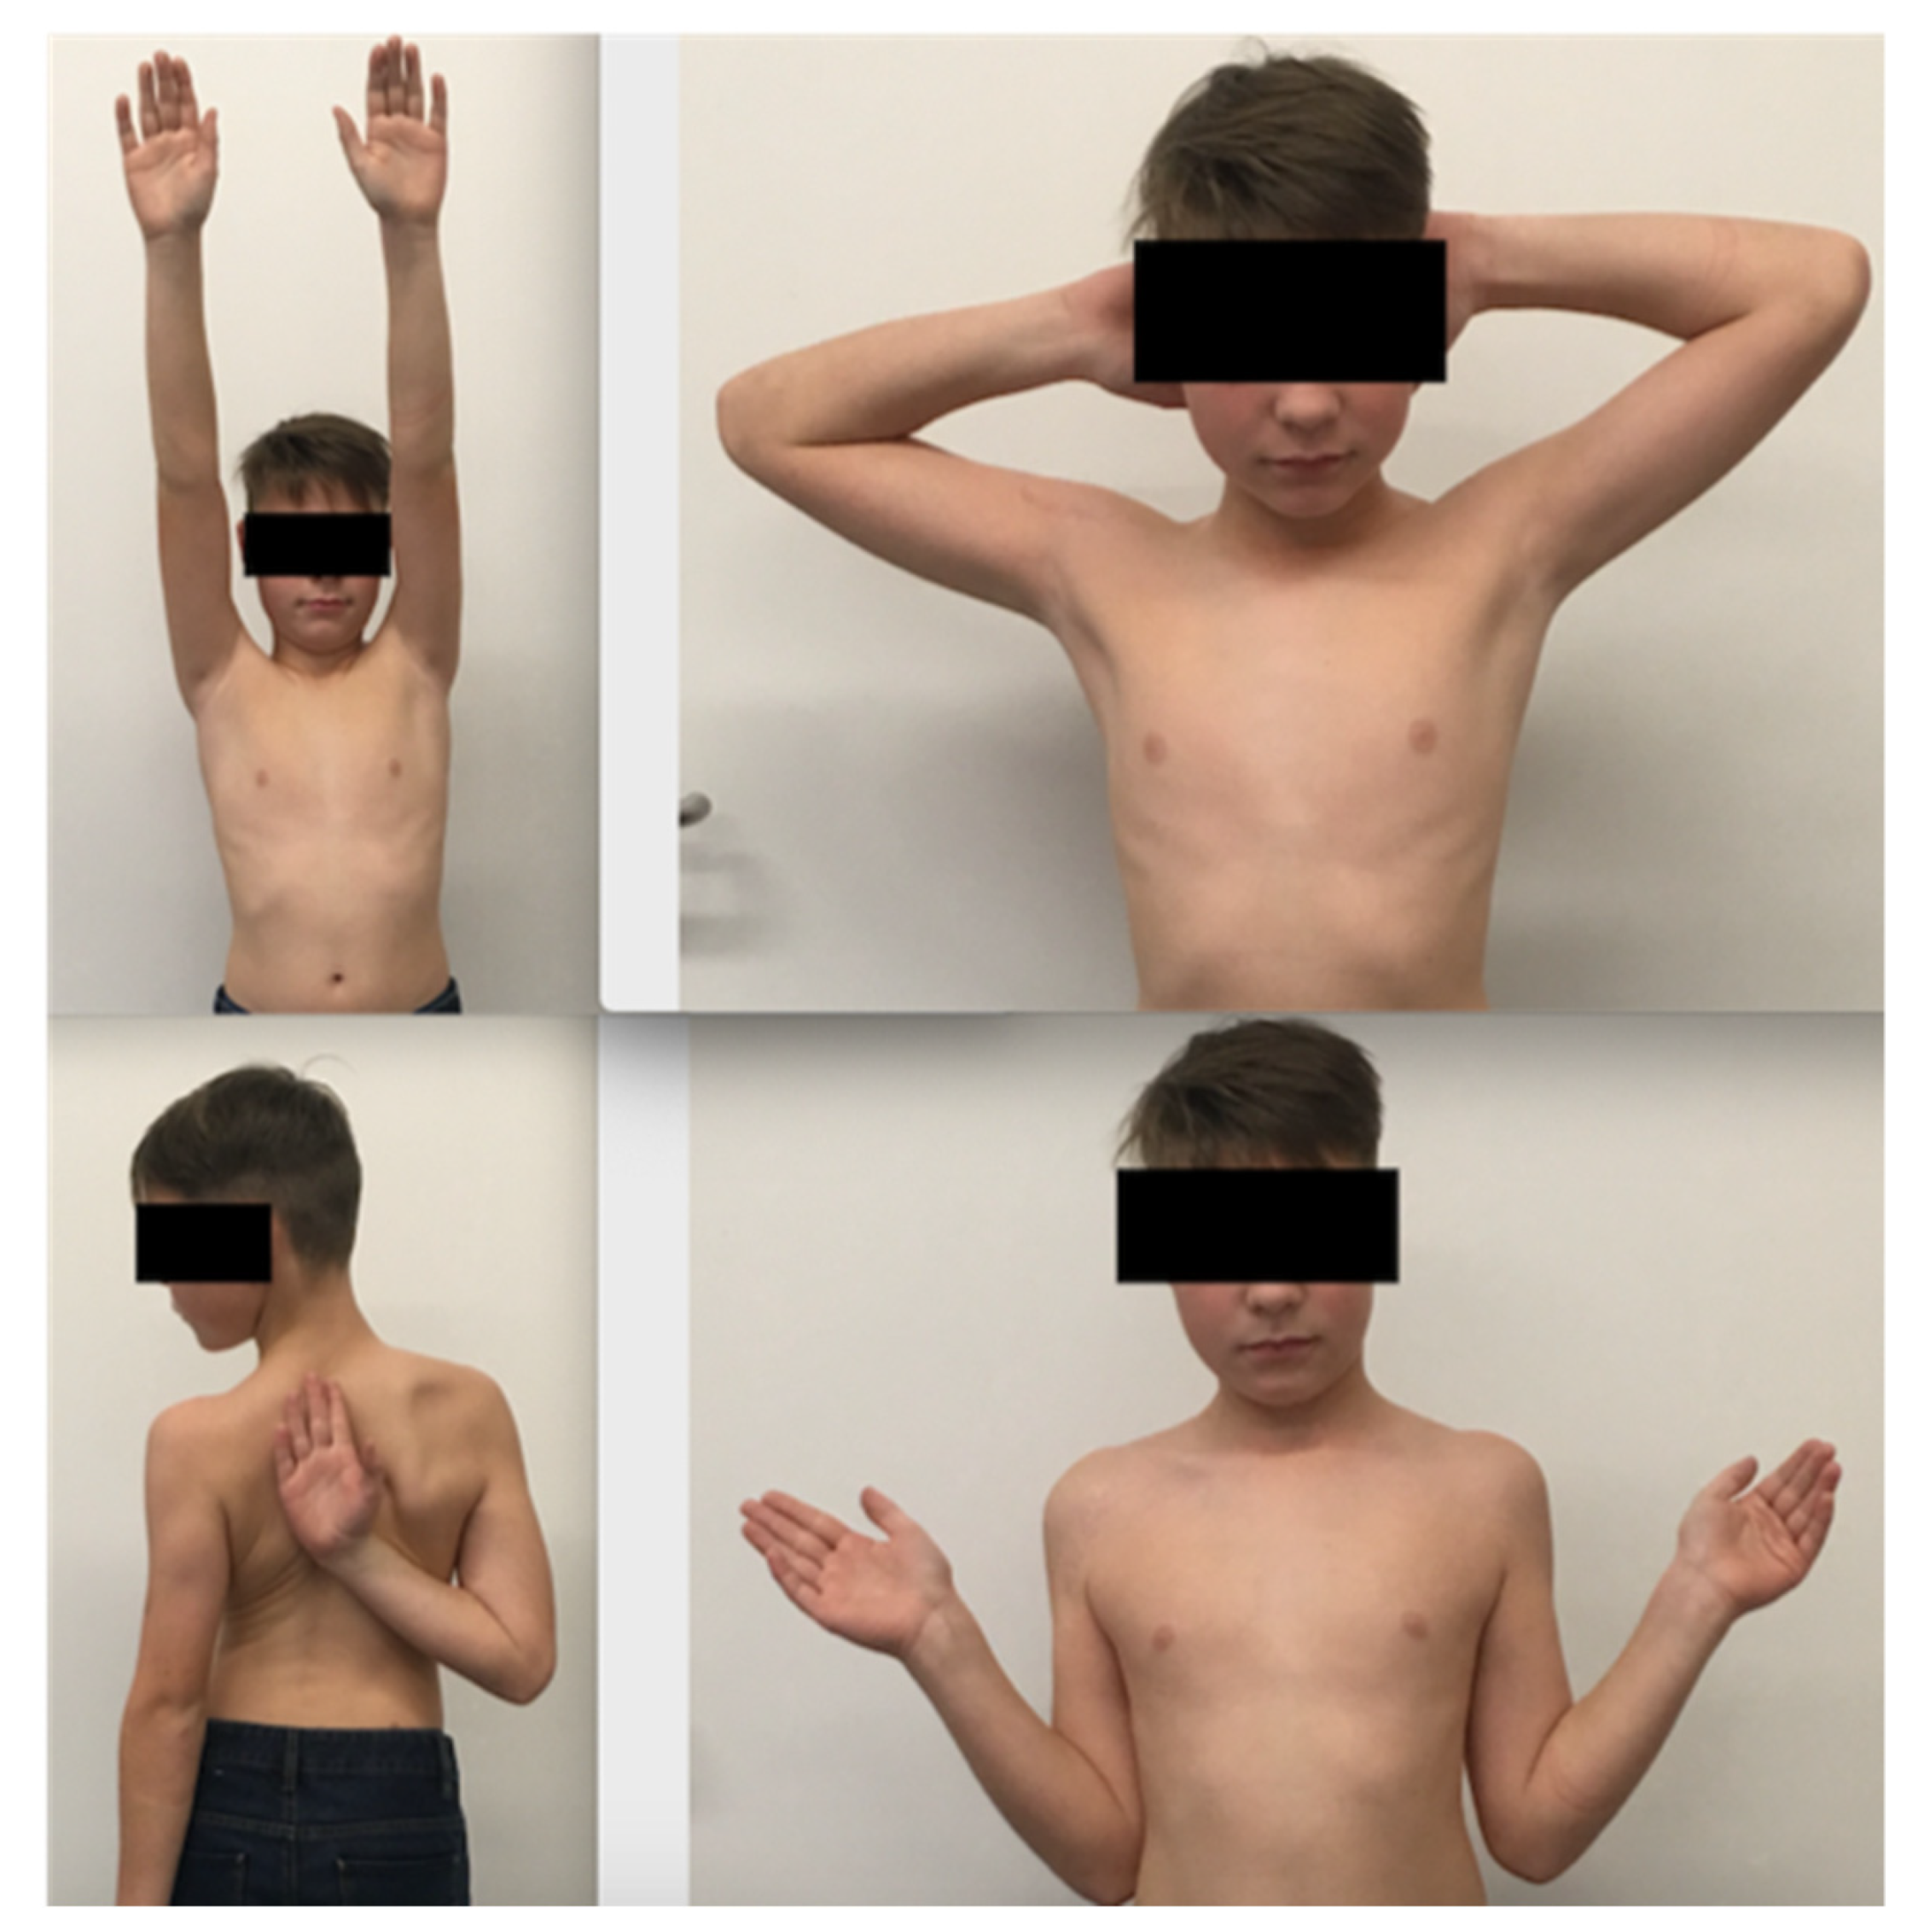

Table 1). The Constant–Murley score at the final follow-up was 97.5 (range 91 to 100) and the mean overall QuickDASH score (including sport and music/work) was 5.5 (range 0–20.8). Analyzing the subtypes of the QuickDASH score, we found a score of 3 for disability (range 0–10), 3.125 for sport and music (range 0–12.5) and 0 for work.

All fractures healed completely, and functional scores were excellent at a 2 year follow-up with symmetrical shoulder movement (

Figure 5). The obstacle to reduction was, in most cases, the entrapped biceps tendon. In one case, the entrapped conjoint tendons inhibited reduction and in one other case periosteal tissue.